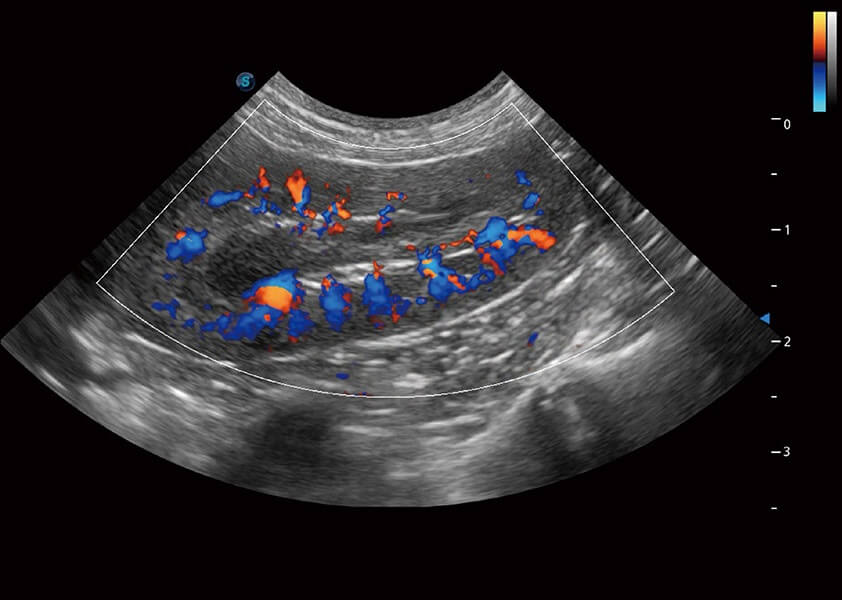

ProPet 60 作為一款高端臺式動物超聲設備,為動物醫(yī)生的日常診斷提供了一系列貼合動物臨床需求、解決臨床實際問題的高級成像功能。憑借全系列高清探頭,滿足醫(yī)生對腹部、心臟、生殖、淺表、肌骨等成像的所有需求,切實幫助您提升檢查效率,提高診斷信心。

動物是人類最親密的朋友和最值得信賴的伙伴。開立醫(yī)療也一直致力于探索動物專用的超聲影像解決方案。 全新推出的ProPet系列,是開立在動物超聲影像智能化、專業(yè)化、精準化的一次跨越式革新。動物不能用言語來表述自己的不適,通過超聲影像,ProPet系列搭建了動物醫(yī)生與不同物種溝通的“橋梁”,為動物醫(yī)生注入了“治愈之力”。